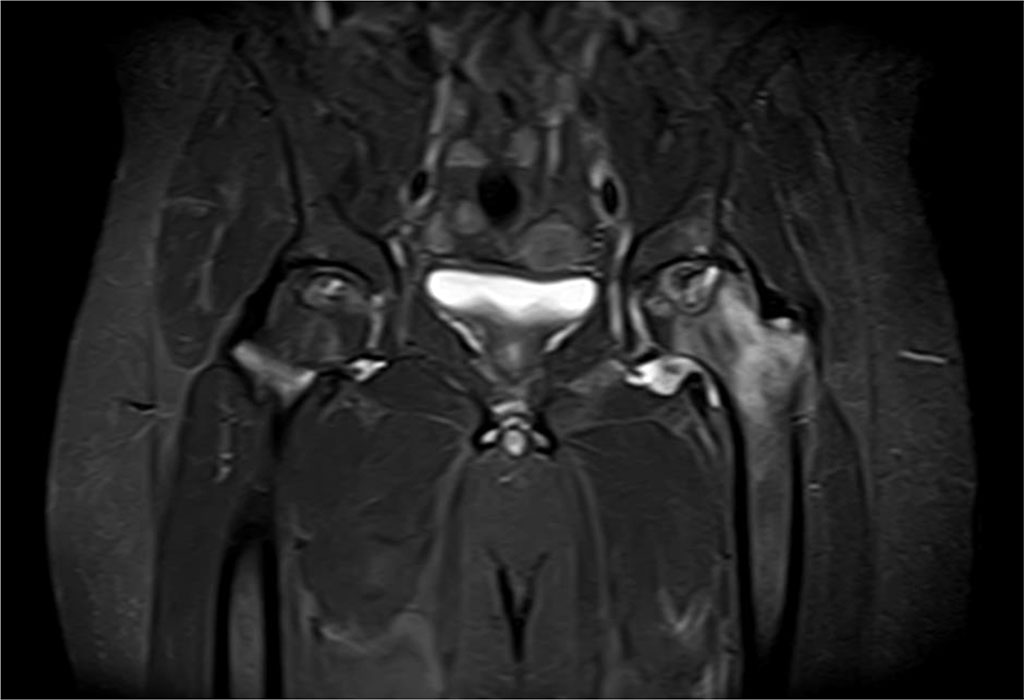

Hip MRI was performed and the problem was detected. The pain intensified after standing up for the last 1 month and hip MRI revealed findings related to stage 2 avascular necrosis in the right hip and stage 3 avascular necrosis in the left hip (Figure 3).

Figure 3. Findings in a 50-year-old male patient with stage 3 avascular necrosis of the left